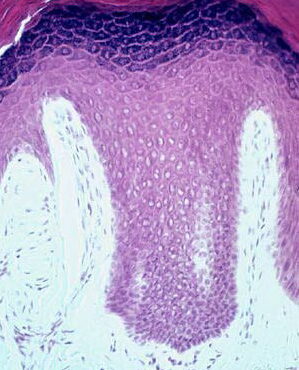

Section of thick skin = مقطع في جلد سميك